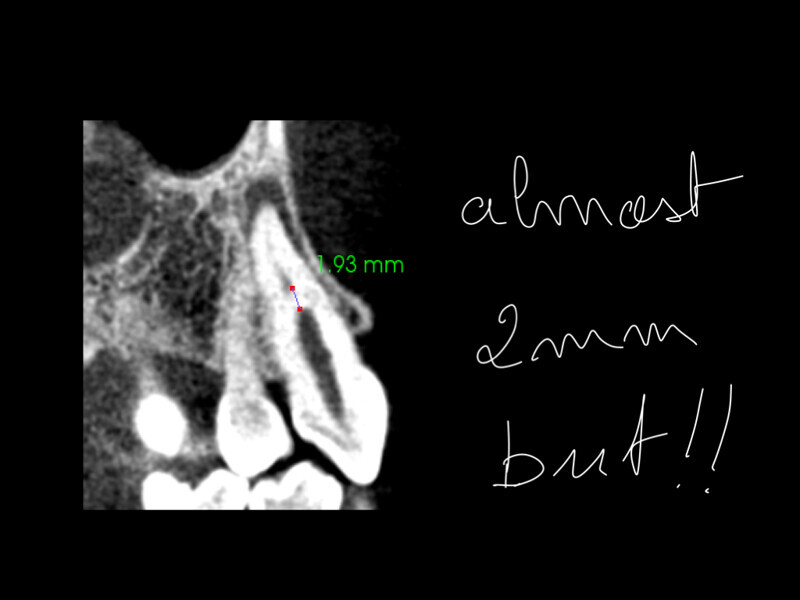

Treatment of the result of chronic activation of substance P